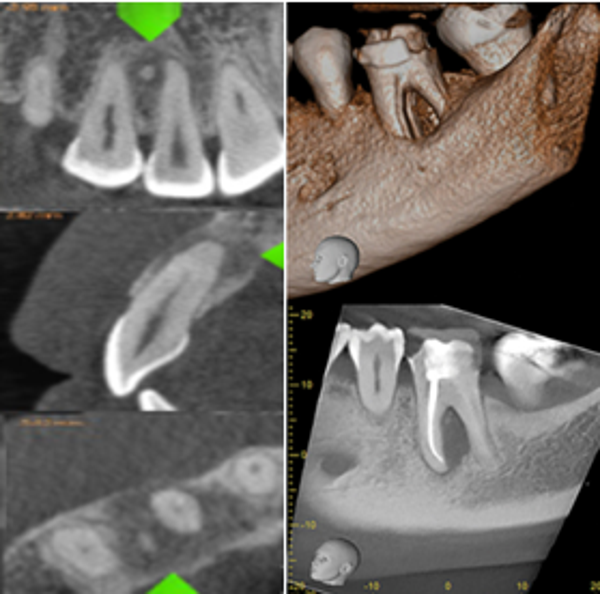

small or Limited Field CBCT

Size 4X4 cm

from 1 to 3 teeth captured.

Endo, Perio. impaction, trauma, supernumerary tooth